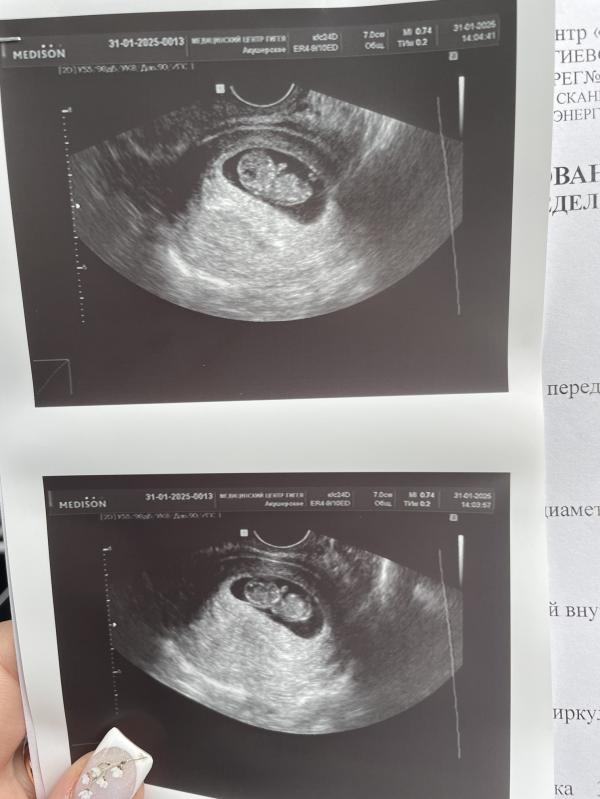

На узи нам 9,5 неделек, теперь жду встречи на первом скрининге😌